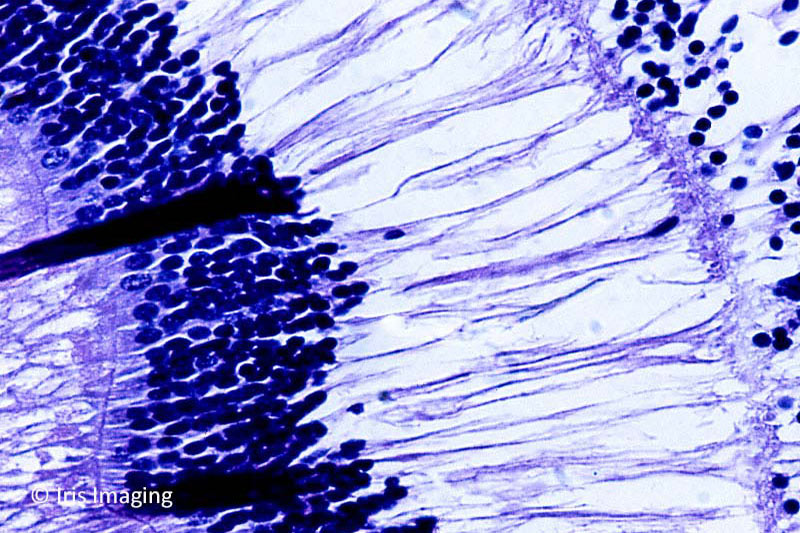

I have primarily earned my living as an ophthalmic photographer. However, I have worked as a photojournalist for daily & weekly newspapers and freelanced covering conflicts in Afghanistan and Central America in the 80’s. I focused on the social and medical issue in conflicts and was able to generate support from the medical community here and overseas.

My knowledge of pathology landed me a position as Community Outreach Coordinator for Cleveland Eye Clinic. I led a team which screened over 45,000 people in NE Ohio communities for vision problems which received national recognition. In the evenings I provided vision screenings for Health Care for the Homeless’ outreach in Cleveland for a number of years.

It was during this time that I started Iris Imaging to provide services to the eye care community of NE Ohio.